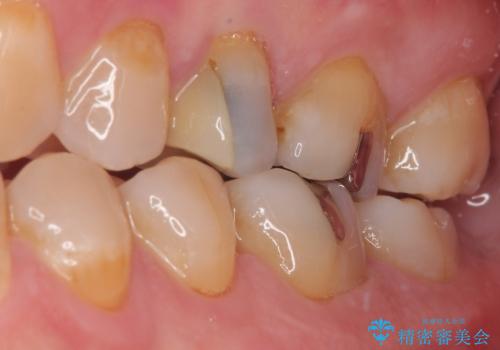

「他の歯も、せっかくなら精度の良いものに替えておきたい」とのご希望があり、

上顎左側第一大臼歯

下顎左側第一大臼歯

に入っていた保険診療の銀歯(メタルインレー)を、精度の良いゴールドインレーへやり替えを行いました。

詰め物や被せ物は、精度が低いと隙間から虫歯(=二次う蝕)になりやすいという問題があります。

精度の高い補綴物を選ぶことで、将来的な治療回数を減らし、歯を長く守ることが可能です。